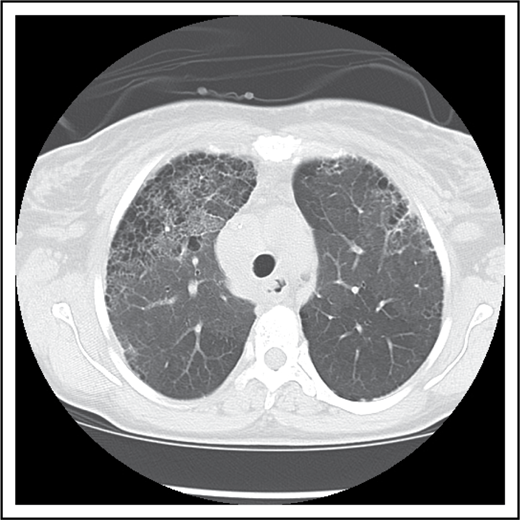

Longitudinal studies suggest that ACS occurs in ∼50% of individuals with SCD over the course of follow-up.3 Repeated episodes of ACS have been postulated to result in development of fibrotic lung disease, which is a restrictive lung disorder evidenced by pulmonary function data and histologic findings of interstitial lung disease ILD and fibrosis37,38 (Figure 1). There are currently no guidelines for the diagnosis of restrictive lung disease in SCD, and epidemiological studies are lacking, but restrictive/fibrotic lung disease occurs most frequently in patients with multiple episodes of ACS and wheezing.39 Fibrotic lung disease can be detected by pulmonary function studies (PFTs) and high-resolution computed tomography of the chest. The most common noted abnormalities include reticular opacities, volume loss, and prominence of central vessels. This was also shown to correlate with lung function abnormalities.33 Taken together, a history of AHR or asthma contributes to the frequency of ACS, which may ultimately lead to development of conditions that are either individually or in combination associated with chronic hypoxia.

Pulmonary fibrosis complicating multiple episodes of ACS. Axial image of the chest computed tomography of a patient with SCD. Extensive fibrotic changes with honeycombing are noted anteriorly; reticular opacities are appreciated with an anterior predominance, and mild ground glass opacities are noted within the lungs.

On further questioning, the patient reported progressively worsening dyspnea over the previous 3 years. He had suffered 5 episodes of ACS and required mechanical ventilation and transfusion for 2 of these episodes. He underwent PFTs, including spirometry, that were suggestive of a moderate restrictive defect with a forced vital capacity of 68% predicted and FEV1 of 60% predicted with a ratio of 89. Restrictive lung physiology was confirmed on plethysmography with a total lung capacity of 63% predicted. His DLco was decreased at 52% predicted after correction for hemoglobin level. An arterial blood gas showed a Pao2 of 52 mm Hg (6.92 kPa) at rest. An echocardiogram was obtained and suggested absence of PH with a TRV jet velocity of 2.4 m/s and a NT-pro-BNP level of 130 pg/mL. A 6MWD put him at a functional capacity of 55% of predicted with desaturation to 76% at the completion of the test. Computed tomography of the chest demonstrated extensive areas of fibrosis (Figure 2).